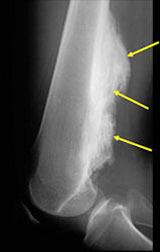

- Large tumors encircle the bone

- Appears to have broad attachment to underlying cortex with a cleft between exophytic base and cortex at periphery. This is referred to as a “String Sign” (cleft is often only identifiable on CT scan)

- There may be invasion of the medullary canal with long standing disease

- High grade or defifferentiated areas may appear as large radiolucent areas/mass adjacent to radiodense areas